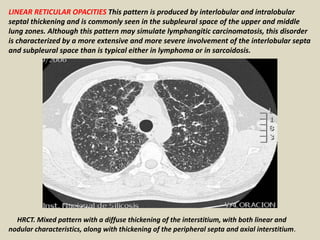

LINEAR RETICULAR OPACITIES This pattern is produced by interlobular and intralobular

septal thickening and is commonly seen in the subpleural space of the upper and middle

lung zones. Although this pattern may simulate lymphangitic carcinomatosis, this disorder

is characterized by a more extensive and more severe involvement of the interlobular septa

and subpleural space than is typical either in lymphoma or in sarcoidosis.

HRCT. Mixed pattern with a diffuse thickening of the interstitium, with both linear and

nodular characteristics, along with thickening of the peripheral septa and axial interstitium.